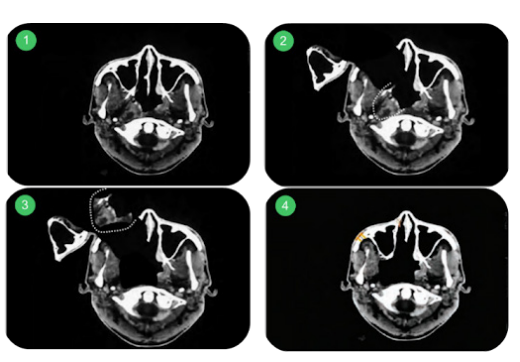

Para acessar tumores profundos (base de língua, amígdala, hipofaringe) sem destruir a face, usamos manobras específicas:

- Mandibulotomia (Swing Mandibular): Serra-se a mandíbula na linha média para abrir a boca como um “livro”, acessando a orofaringe posterior.